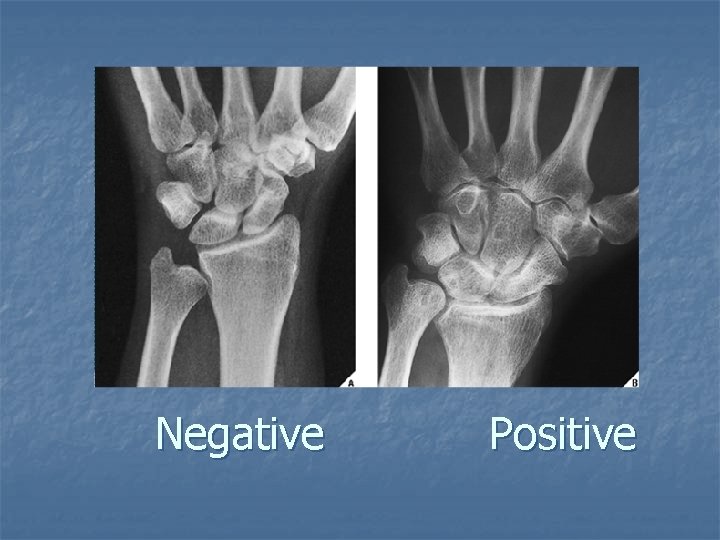

Neutral Ulnar variance

Negative Positive